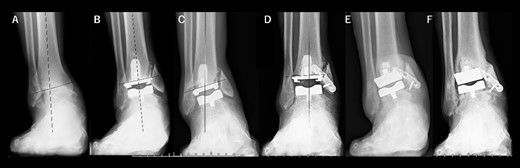

A 76-year-old woman with a 25-year history of RA [Clinical Disease Activity Index (DAS28-CRP score) 2.45: good control] had a JSSF ankle/hindfoot scale score of 42 points. She had been treated with 6 mg of methotrexate (MTX) per week. She complained of difficulty walking and ankle pain, resulting in an awkward gait. Talar tilt was 17° varus (Fig. 2A). She underwent TAA with medial malleolar osteotomy without internal fixation, and the tibial component was placed in the 2° varus position (Fig. 2B). Three years after TAA, she missed two or three steps while walking down the stairs. and developed anterior tibial pain. Radiography showed that varus migration of the tibial component had progressed (7° varus position; Fig. 2C), and she required revision TAA with internal fixation using a plate and allograft bone transplantation (Fig. 2D).

Radiographs of preoperative weight-bearing radiograph of the antero-posterior ankle joint in Case 2. (A) Preoperative. Talar tilt is 17° varus. Opening of the lateral gutter is seen. (B) One month after surgery. Medial malleolar osteotomy without internal fixation and the tibial component placed in the 2° varus position. Opening of the lateral gutter remains. (C) Three years after surgery. Varus migration of the tibial component has progressed after the patient missed the stairs (7° varus position of the component), and nonunion at the medial malleolar osteotomy has occurred. Opening of the lateral gutter has also remained. (D) Three months after revision surgery. Medial malleolar osteotomy site is fixed with a plate, and varus positioning of the tibial component still remains (3° varus). The lateral gutter is closed.